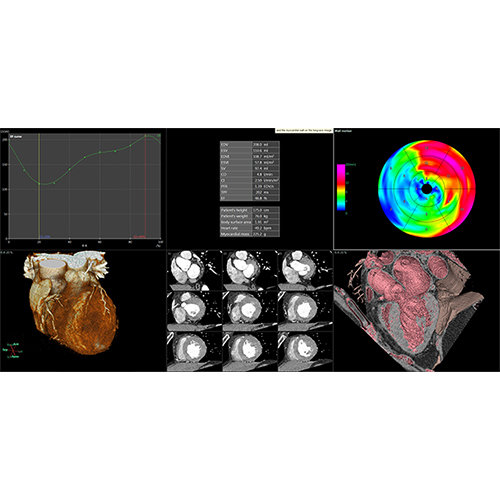

ANYTHINK 经导管主动脉瓣膜置换术分析系统